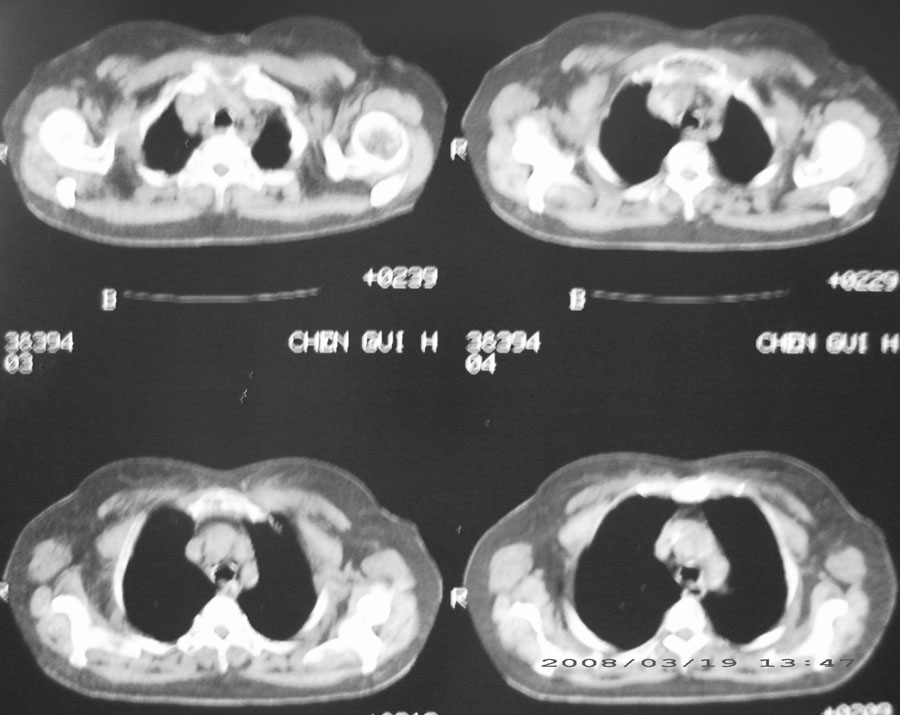

标题: CT13104:胸部大家看看啊,第一次发啊, [打印本页]

标题: CT13104:胸部大家看看啊,第一次发啊,

粟粒性结核

细支气管肺泡癌

本病例主要是癌性淋巴管炎与结节病的鉴别。好好查查吧。

密漫性沿纹理走行小结节影;有间质纤维化;可考虑尘肺;以图而论

血行播散性肺结核

双肺网状结构,小叶间质结节状增厚,考虑结节病

综合大家意见,结核、结节病、肺泡细胞癌均有可能,间质性肺炎暂不考虑,病灶纠集不明显,纵隔未见钙化淋巴结,尘肺可能性不大,但还是要密切结合临床诊断。

今天重新仔细看了看,矽肺确实不能除外,病灶主要表现为间质结节及纤维化。好好问问病史吧。